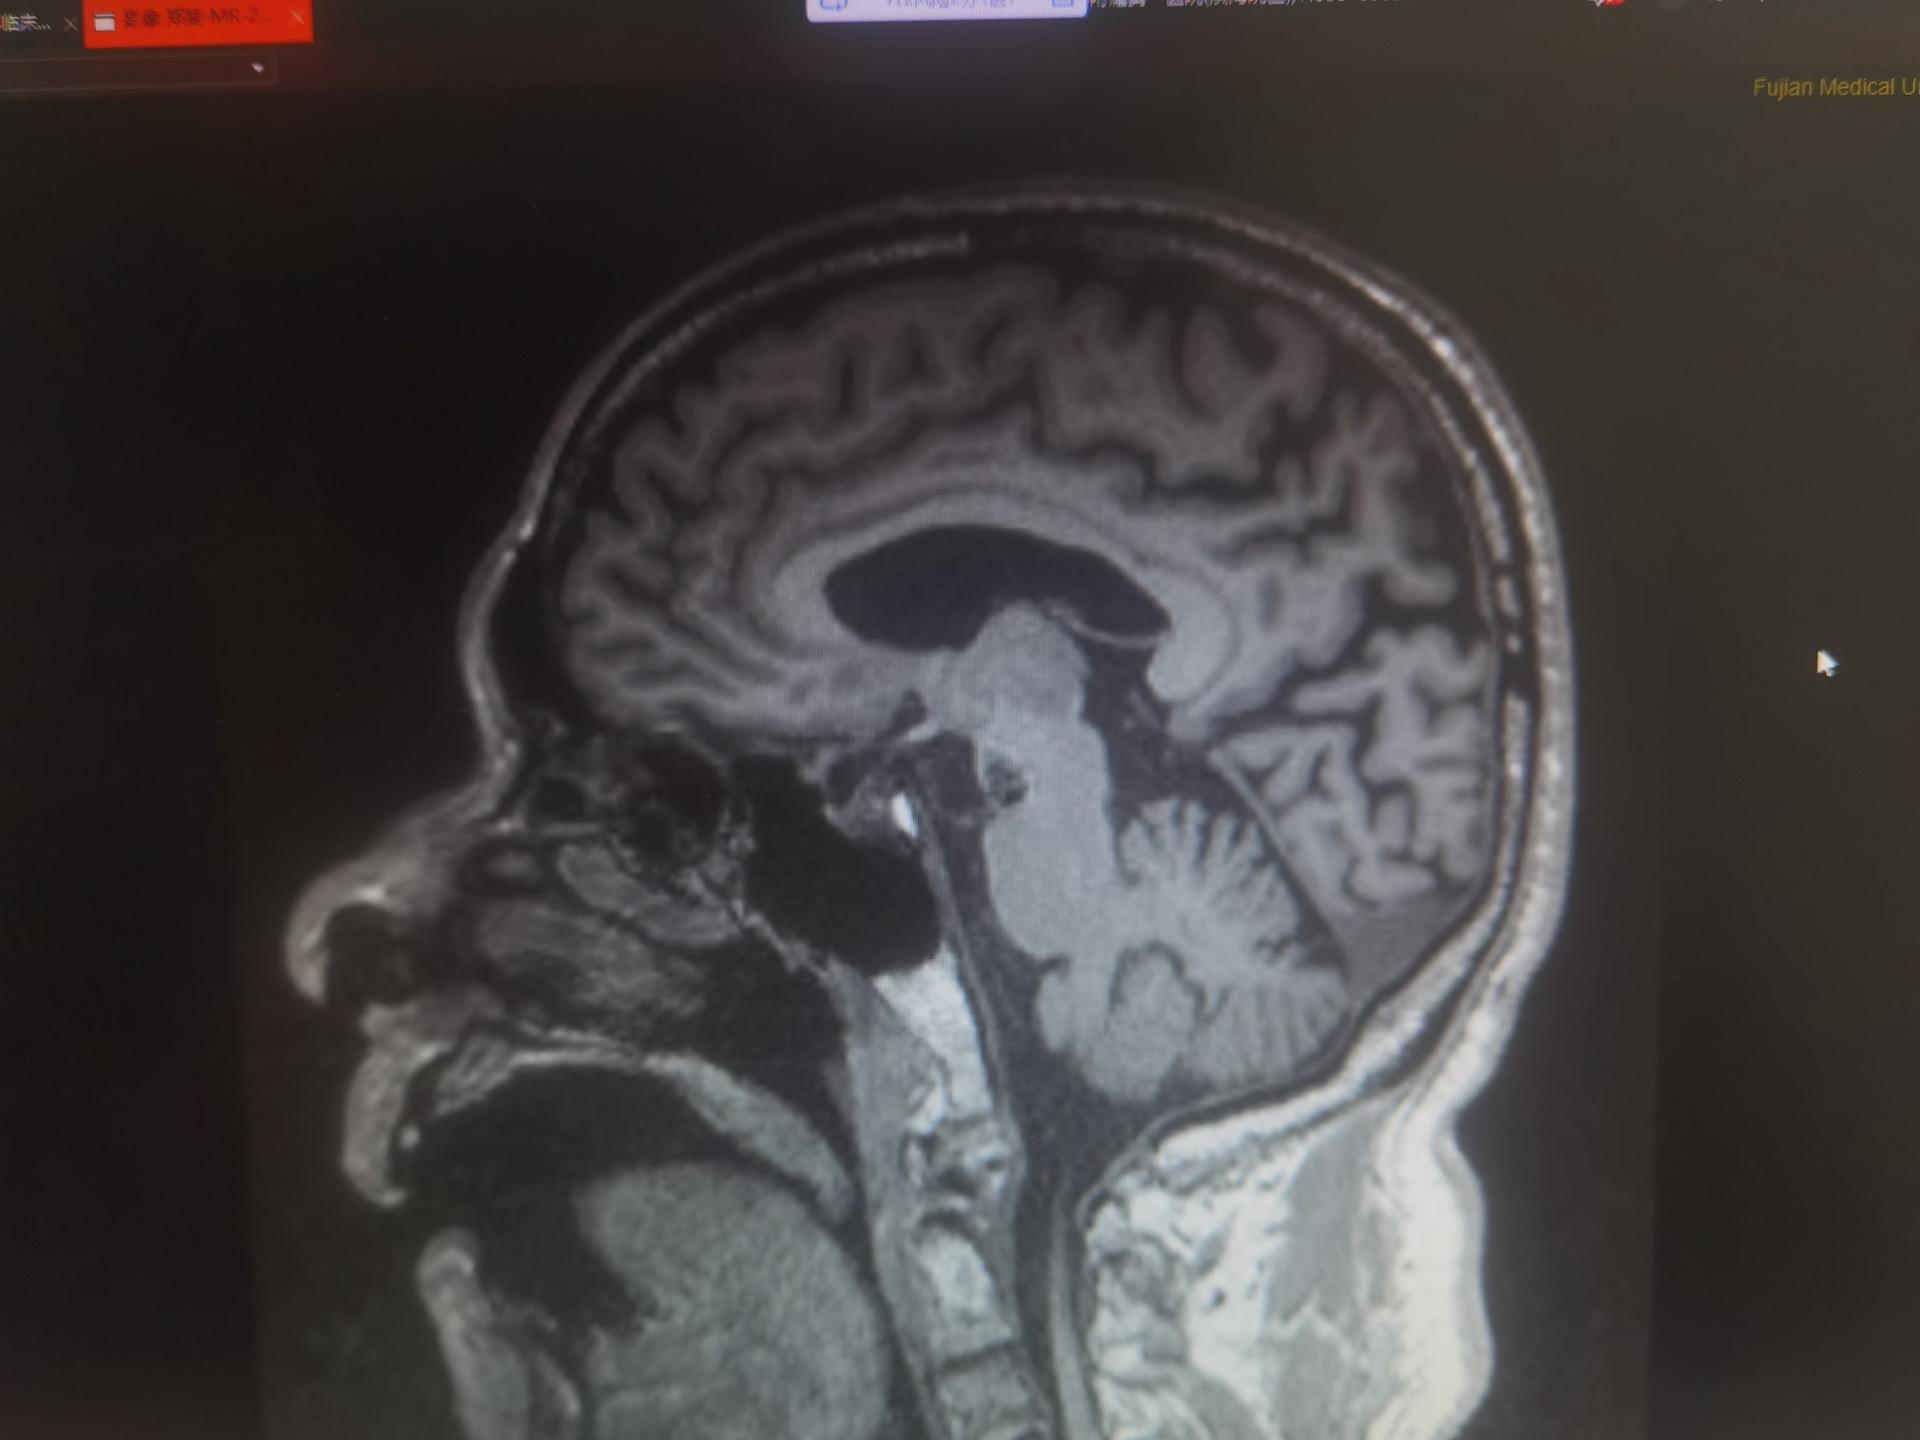

抗“帕”治疗,我们一直在路上!分享一位特殊帕金森患者,居然在右侧STN核团“盘踞”着一个海绵状血管瘤,采用非对称性靶点,得益于复合手术室和导航系统,术中即刻CT重建, 侧方误差在0.1-0.3mm,深度误差小于0.1-0.8mm